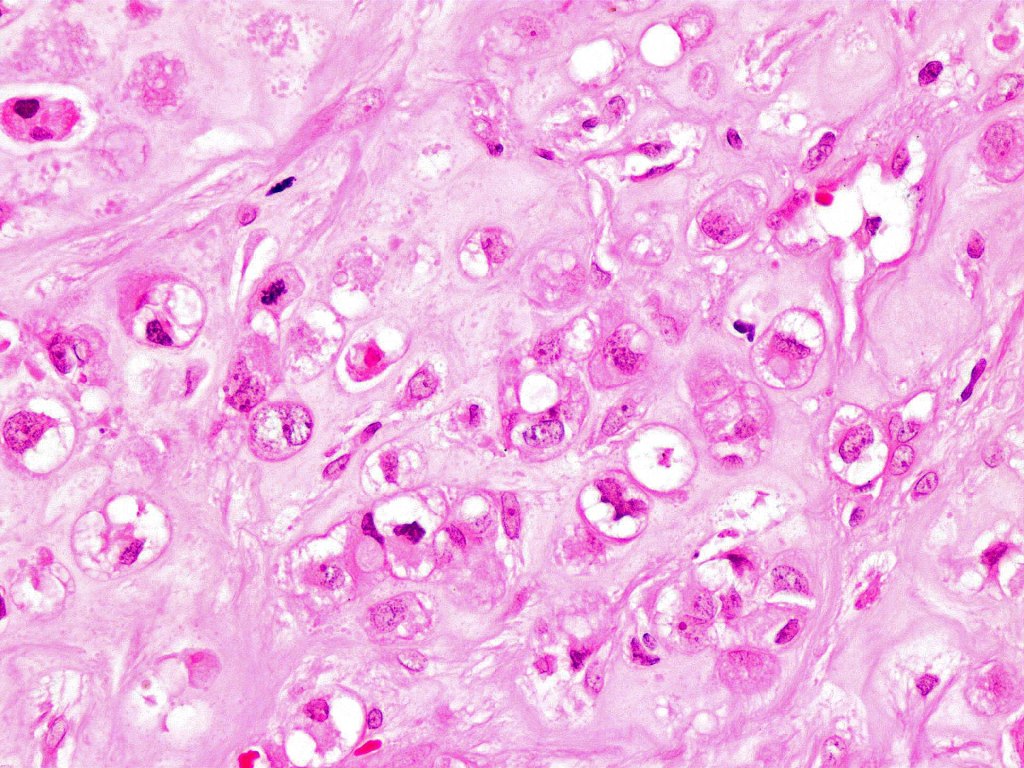

•Admixture of squamous carcinoma & pleomorphic spindled cell, osteoid, chondroid, MFH-like +/- osteoclast-like giant cells & rarely, smooth muscle, skeletal muscle, myofibroblastic or angiosarcomatous elements

•Epithelial component AE1/AE3, CK5/6 & p63 +ve;

•Mesenchymal element variable CD10, CD68, CD99 & lineage specific markers +ve; scattered cells may show weak keratin expression